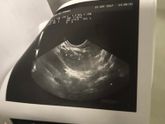

Девочки, все тесты показывают две палочки, клиа блю 2-3 недели .были все признаки - тошнота, очень болела грудь, частое мочеиспускание. И вот уже второй день как тишина . Ничего не происходит. Я насторожилась . Сходила к врачу . Сделали первое узи … Читать далее